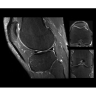

Поле обзора 50x50x50 см и апертура шириной 70 см позволят достоверно визуализировать сложные анатомические области для пациентов с крупным телосложением, например, плечи и бедра. Феноменальная однородность системы SIGNA Architect обеспечивает наиболее широкое поле обзора с улучшенными характеристиками градиентов. Ничто не останется незамеченным.

• OrthoWorks — программное решение для визуализации структур опорно-двигательного аппарата с прекрасным контрастированием тканей.